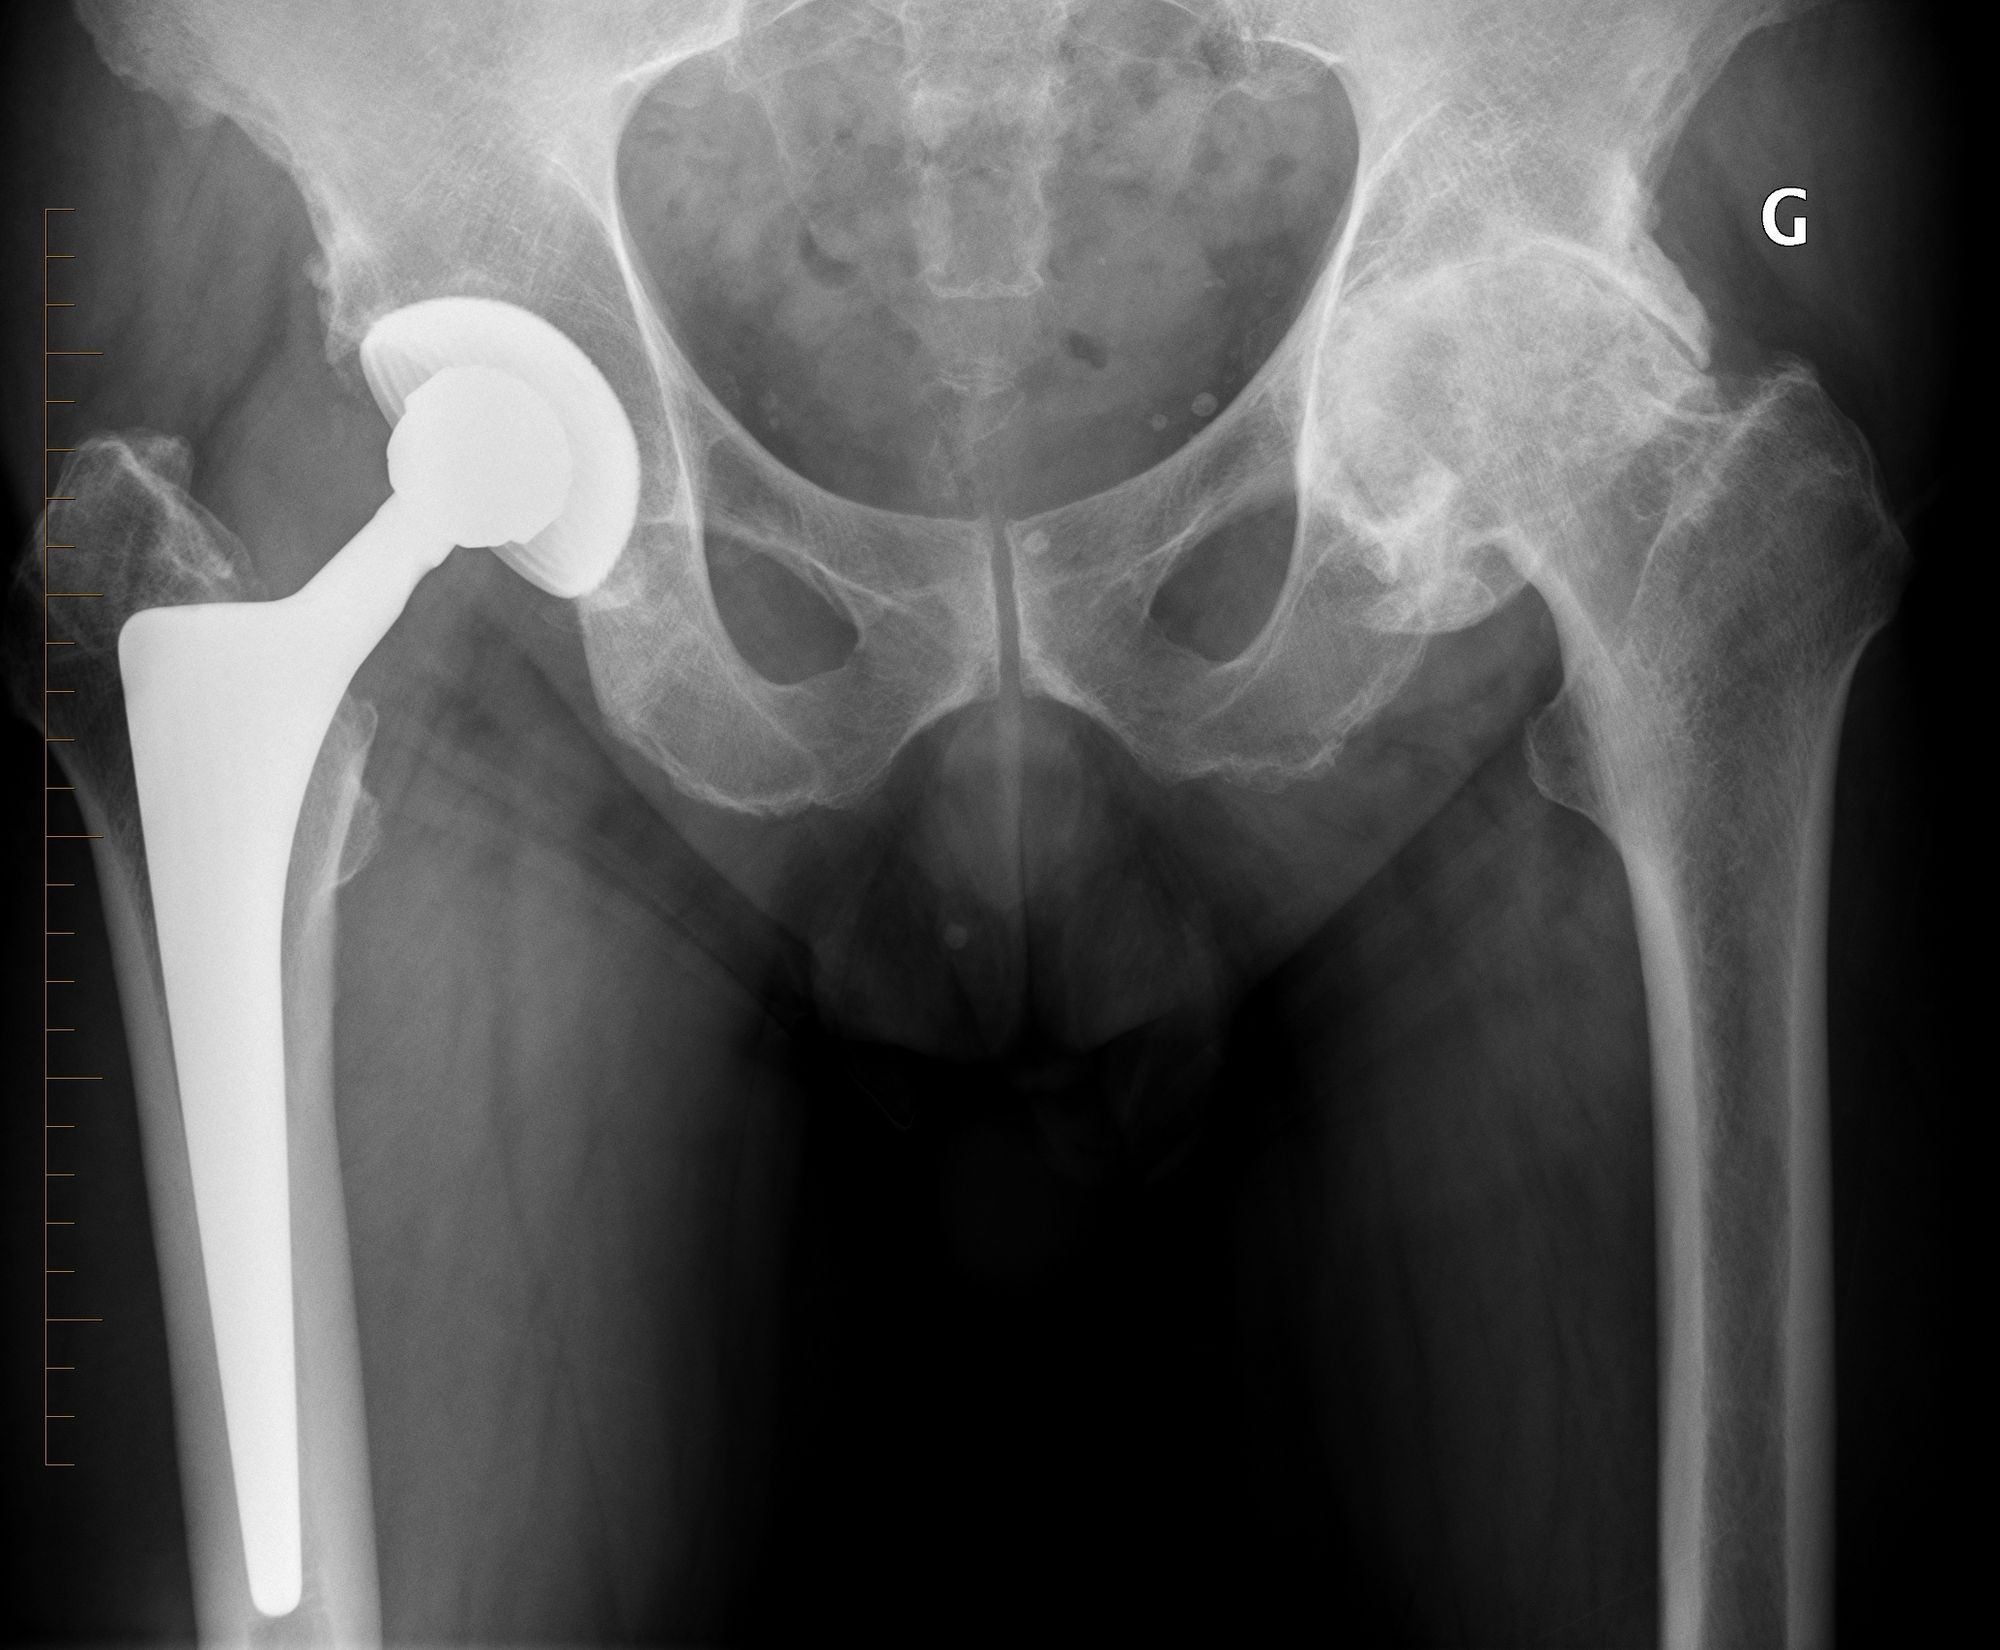

Using an LDH THA allows unrestricted movement after THA, for all types of surgical approaches. Vendittoli’s group in Canada does not impose any postoperative ROM restrictions for the posterior surgical approach, as it simplifies the patient education process, boosts their confidence during rehabilitation, and facilitates bilateral procedures[15,16]. LDH monobloc DM is especially interesting for many older women with large thighs and a small acetabular cavity (<50mm, Fig. 7).

In these cases, standard bearing diameters are prone to instability. With an LDH, a DM design provides optimal implant stability for these not-so uncommon patients. Moreover, with LDH we do not impose any activity restrictions in the long term. LDH CoC THA offers a major benefit for many active individuals since they can return to their regular jobs (e.g. plumber, roof worker, police officer, fireman) as well as for those who want to practice sports like rock climbing, kayaking, water skiing and martial arts.

Given the single neck diameter of most femoral stem designs, the head–neck ratio increases proportionally with the head diameter. Theoretically and clinically, this leads to a greater hip range of motion [18,19]. In addition, due to a supraphysiological arc of motion, extraarticular impingement is the first to occur whilst inter-component impingement is rare. Consequently, less-than-optimal implant positioning can be much better tolerated[20]. This is an important point considering the extent of surgical indications for patients with primary or secondary anatomical deformations (e.g. dysplasia, acetabular retroversion, previous pelvic osteotomy, post traumatic), because achieving an optimal implant position is often challenging (Fig. 7).

For the older, more sedentary and those with a shorter life expectancy, DM LDH THA is the ideal alternative (Figs 7 and 8).